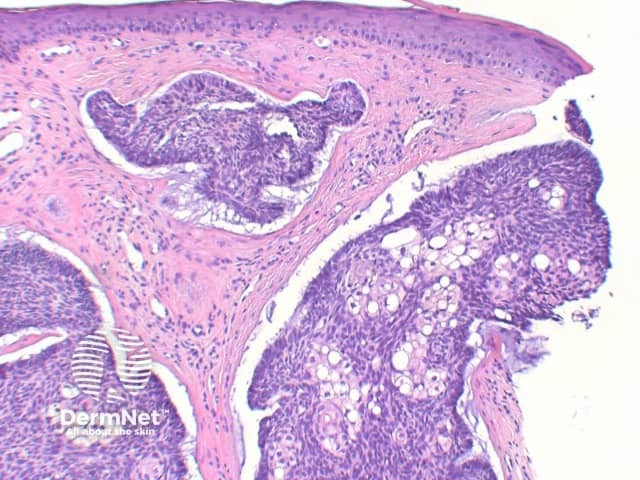

Sebaceous differentiation: Basal cell carcinoma can also occasionally show areas of significant sebaceous differentiation (figure 12). This needs to be differentiated from sebaceoma, as discussed below.

The key feature of basal cell carcinoma at low power magnification is of a basaloid epithelial tumour arising from the epidermis (figure 1). The basaloid epithelium typically forms a palisade with a cleft forming from the adjacent tumour stroma (figure 2). Centrally the nuclei become crowded with scattered mitotic figures and necrotic bodies evident (figure 3). A useful distinguishing feature from other basaloid cutaneous tumours is the presence of a mucinous stroma (figure 4). Some tumours may also show foci of regression, seen as areas of eosinophilic stroma with lack of basaloid nests.

Infundibulocystic BCC: This variant shows multiple small cysts containing cornified material with differentiation towards the infundibulum. In distinguishing from trichoepitholioma, it lacks papillary mesenchymal bodies, but frequently retains a mucinous stroma.